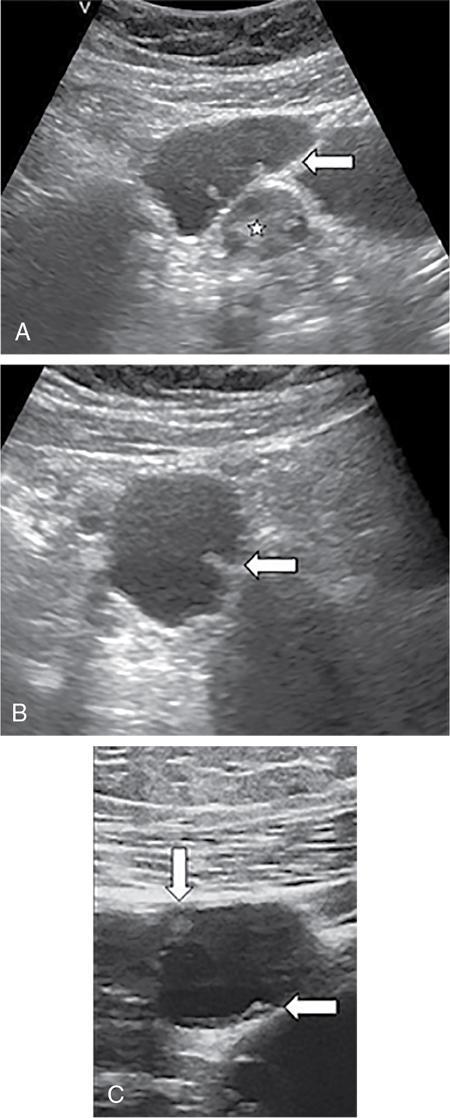

Venkatraman Indiran Bridging vessel sign Multiple vascular channels (white arrows) connecting uterus (black arrow) to an adjacent pelvic mass on imaging studies, is known as the ‘bridging vessel’ or ‘bridging vascular’ sign. Originally described on colour Doppler imaging, but also seen on computed tomography (CT) or magnetic resonance imaging (MRI). Helps in differentiating a mass of uterine origin, typically a subserosal fibroid, from other pelvic masses. Sensitivity and specificity of ‘bridging vessel sign’ in identifying subserosal fibroids range from 90% to 100%. (Best seen when subserosal fibroid is larger than 3 cm in diameter.) Ovarian masses invading the uterus may rarely produce a falsely positive bridging vessel sign. Broccoli sign Submucosal uterine leiomyoma prolapsing into the endocervical canal, along with its stalk in the uterine cavity on sagittal T2-weighted images together is called as ‘broccoli sign’ (white arrow). Submucosal uterine leiomyoma Bunch of grapes Intrauterine mass with cystic spaces without any associated foetal parts on ultrasound (white arrows) classically gives a ‘snow storm’ or ‘bunch of grapes’ appearance. Complete hydatidiform mole Hourglass sign Deep infiltrating endometriosis (DIE) affecting the posterior urinary bladder wall, usually in the midline, causes loss of its distensibility, resulting an hourglass configuration of urinary bladder. Deep infiltrating endometriosis (DIE) Hyperechoic line sign Normal endometrium surrounding the endometrial polyp on ultrasound appear as a hyperechoic rim on transvaginal ultrasound is called as ‘hyperechoic line sign’. Hyperechoic line sign represents a focal intracavitary lesion. Endometrial polyp Indian head dress sign/moose antler sign In deep infiltrating endometriosis (DIE), adhesions between the anterior wall of rectosigmoid and posterior wall of uterus, stretches the muscular layer of the bowel and creates an infiltrative nodule with parallel lines that extend from the adhesion to the rectosigmoid. This is called as ‘Indian head dress sign/moose antler sign’ (white arrow). This is seen on sagittal T2-weighted images as well as transvaginal ultrasound. Deep infiltrating endometriosis (DIE) Interstitial line sign An echogenic line that extends into the upper regions of the uterine horn and borders the margin of the intramural gestational sac is called as the ‘interstitial line sign’ (white arrow). Seen best on transabdominal/transvaginal ultrasound. Specific finding of interstitial pregnancy Mushroom cap sign Mushroom-shaped lesion which is seen displaced into the bowel lumen in patients with solid invasive endometriosis of the rectosigmoid colon on axial or sagittal T2-weighted MRI is called as ‘mushroom cap sign’ (red box and white arrow). Low signal intensity base of the mushroom corresponds to hypertrophy and fibrosis of the muscularis propria, whereas the high intensity cap represents oedematous mucosa and submucosa. Deep infiltrating endometriosis (DIE) Pedicle artery sign Feeding vessel sign Central vessel entering the endometrium from the surrounding myometrium colour Doppler imaging of the endometrium in endometrial polyps is called as pedicle artery sign (white arrow). Endometrial polyps in women with postmenopausal bleeding. (Sensitivity of 76.5%; specificity of 95.3%.) Popcorn ball calcification Dense, amorphous calcifications of uterine fibroids seen on the plain radiographs is called as ‘popcorn calcification’ (white arrow). Confluent, coarse calcification constitutes the most specific radiographic sign of a benign uterine fibroid; but only 10% or fewer of fibroids show calcification. Question mark sign of uterus The uterine corpus that is flexed backward with the fundus of the uterus facing the posterior pelvic compartment and the cervix directed anteriorly toward the urinary bladder, is called as question mark sign of uterus (white arrow). Also called as comma-shaped uterus. 93% specificity and 75% sensitivity in diagnosing adenomyosis uterus. Sliding organs’ sign When the uterus and ovaries glide freely over the posterior and anterior organs (such as rectum and urinary bladder, respectively) during real-time dynamic transvaginal sonography, it is called as ‘positive sliding organs’ sign’. In case of adhesions due to endometriosis, free gliding of organs is absent and is called as negative sliding sign. Snowstorm sign Grainy appearance with low-level homogeneous internal echoes which move slowly downward due to their viscosity seen in endometrioma on transvaginal ultrasound is called as snowstorm sign. Endometriomas Split fibre sign Presence of curvilinear T2 hypointense strands within the degenerated leiomyoma separated by the fluid accumulation and oedema is called as the ‘split fibre’ sign. Split fibre sign on T2-weighted MRI can be used to differentiate hydropic degeneration from other conditions like malignant change. Three-line sign or triple line sign or trilaminar appearance Shortly before ovulation, two additional bright linear echoes outline two hypoechoic layers of endometrium with a central hyperechoic line in the endometrium (white arrow). It is called as the ‘three-line sign’ or ‘triple line sign’ or trilaminar appearance. A triple-line pattern with a moderate endometrial thickness is associated with a good clinical outcome on in-vitro fertilization. Venetian blind shadowing Also known as ‘rain shower’ appearance Heterogeneous myometrial appearance due to hyperechoic heterotopic endometrial tissue and hypoechoic hyperplastic smooth muscle appearing as vertical linear bands of shadows on ultrasound is called as ‘Venetian blind shadowing’. Classically described in uterine adenomyosis; sometimes in uterine fibroids also. Bead on strings sign Thickened endosalpingeal longitudinal folds within a dilated fallopian tube without wall thickening appears as small mural nodules on cross-sectional images on ultrasound is called as ‘bead on strings’ appearance. Seen in chronic salpingitis Beaded tube Multiple constrictions along the course of fallopian tube may form due to scarring is seen in genitourinary tuberculosis and shows a ‘beaded’ appearance. Female genital tuberculosis Cogwheel sign Thickened endosalpingeal longitudinal folds within a dilated fallopian tube with thickened wall appears as small mural nodules on cross-sectional images across the long axis of the fallopian tube on ultrasound (white arrows) produce a characteristic ‘cogwheel’ appearance. Seen in acute salpingitis. The presence of thickened longitudinal folds is pathognomonic for hydrosalpinx. Cobblestone tube Rounded filling defects in cases of fallopian tube tuberculosis are called as the cobblestone pattern. Is an effective radiographic sign of intraluminal scarring and adhesions. Female genital tuberculosis Golf club tube Occlusion of the isthmus or fimbrial end of the fallopian tube and filling up of the tube with serous or clear fluid produces a moderate dilatation at the fimbrial end, produces a ‘golf club–like appearance’. Female genital tuberculosis Halo sign Thin radiolucency seen separating the loculated peritubal collection from the dilated tube, is known as the ‘halo sign’. This radiolucent halo represents the thickened wall of the tube. Female genital tuberculosis Incomplete septation sign Thin linear structures appearing to protrude into the tubular cystic adnexal structures, but not touching the opposite walls is called ‘incomplete septation sign’ of hydrosalpinx. Apparent septae are due to apposition of the inner walls of the dilated and folded fallopian tube. Hydrosalpinx Pipe stem tube Rigid contour of the fallopian tube seen in cases of fallopian tube tuberculosis is called as ‘pipe stem appearance’. Female genital tuberculosis Leash sign Typical eccentric leash of vessels on colour Doppler (white arrow) showing a low resistance placental type of flow on spectral Doppler in fallopian tube ectopic pregnancies is called as leash sign.